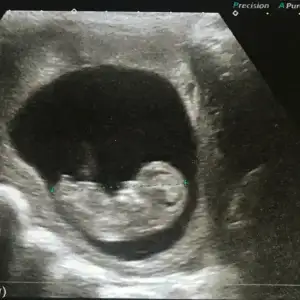

Benim kan pıhtı problemim dışında damarlarımda yüksek derece de tıkanma olduğu için coraspirin verdi doktor.Kızlar bende clexan kullanıyorum ama coraspin yok bu pıhtılaşma yok etkileyen genle mi ilgili acaba sizde hangi gen

ler de vardı sıkıntı bende pai 4g5g heterozigot

Damarlarımda problem olmasa coraspirin eklenmeyecekti.